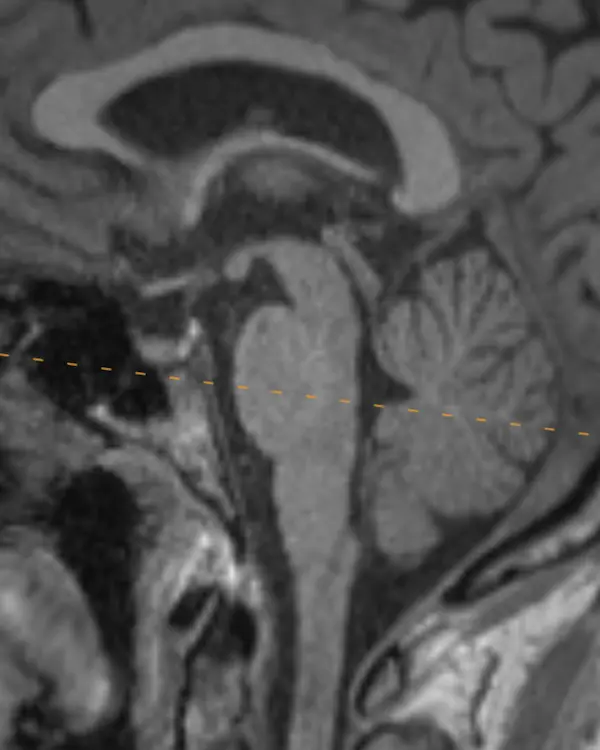

Note that axial planes in brain imaging are not perfectly perpendicular to the brainstem, they are instead created by drawing a line through the anterior commissure (AC) and posterior commissure (PC); the so-called AC-PC line. Keep this in mind when correlating the appearance of structures in the axial plane to sagittal.

Trigeminal Nerve in Sagittal

The two most important trigeminal nuclei are the main sensory and motor nuclei, introduced above. The mesencephalic and spinal nuclei are elongated and span the majority of the brainstem. Their approximate location in the axial plane will be introduced in the next level.

The name trigeminal comes from its three divisions: ophthalmic (V1), maxillary (V2), and mandibular (V3). This split occurs at the trigeminal ganglion, located in a CSF space beside and below the cavernous sinus called Meckel's cave.